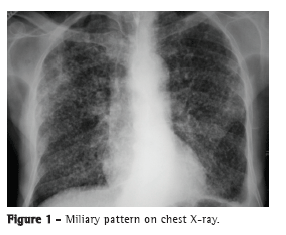

The most common radiological findings are reticular infiltrates and consolidation,(5,6,10,15,17) and cavitation can occur in 27-50% of cases.(6,10,16) Figures 1 to 4 show some of the main radiological patterns in this context.

The time from onset of symptoms to initiation of antituberculosis treatment has been reported to be over 30 days in 28.8-34.0% of cases.(6,17) The time from admission to initiation of appropriate treatment was evaluated in only one study, which reported a mean of 4.3 days. In that retrospective study, the time from admission to initiation of treatment was shorter in patients with miliary tuberculosis than in those with tuberculous pneumonia (2.8 ± 2.5 days vs. 5.0 ± 7.0 days; p = 0.048).(16) There can be a delay in diagnosis and, consequently, in initiation of treatment because it is difficult to differentiate tuberculous pneumonia from severe bacterial pneumonia on X-rays. Considering this difficulty in distinguishing the two pathologies, one study evaluated the differences between ICU patients with severe pneumonia and tuberculosis and those with severe pneumonia without tuberculosis in terms of their clinical and radiological characteristics. Symptom duration longer than two weeks and the presence of micronodules or a cavitary pattern on chest X-ray were significantly associated with active pulmonary tuberculosis.(20) In addition, a miliary pattern on chest X-ray can also be misinterpreted as congestive heart failure.(18)